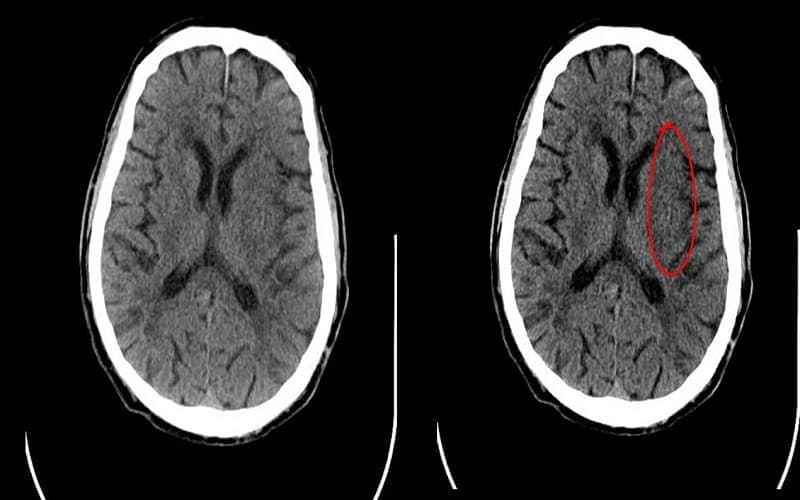

2.2. Giảm tỷ trọng nhu mô não

Ở giai đoạn tiến triển, vùng não bị thiếu máu sẽ xuất hiện giảm tỷ trọng do phù và hoại tử mô. Đây là dấu hiệu điển hình khi chụp CT nhồi máu não, phản ánh rõ khu vực não bị tổn thương theo vùng cấp máu của động mạch. Mức độ giảm tỷ trọng càng rõ thì tổn thương càng nặng và lan rộng.

2.7. Tổn thương theo vùng cấp máu động mạch

Ở giai đoạn muộn hơn, vùng nhồi máu sẽ hiện rõ là khu vực giảm tỷ trọng theo lãnh thổ cấp máu của động mạch bị tắc (như động mạch não giữa). Đây là đặc điểm điển hình giúp xác định chính xác phạm vi tổn thương khi thực hiện chụp CT nhồi máu não.